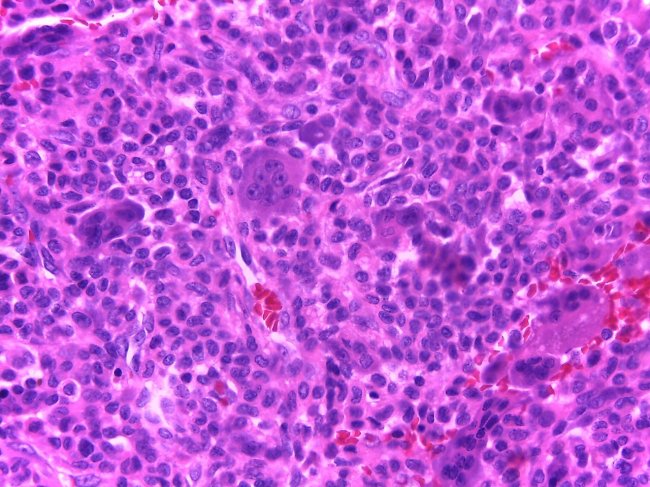

- Exame histológico: Quando observado ao microscópio o material colhido através de uma biopsia é que é possível confirmar o diagnóstico de cancro.